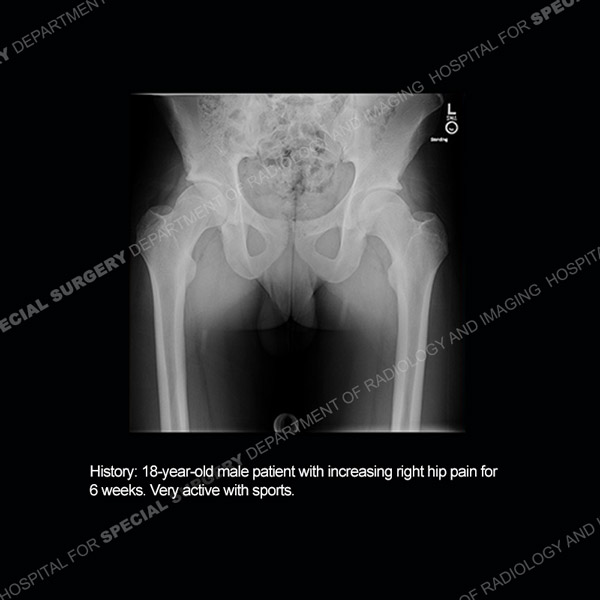

Featured Case of the MonthCase 216: 29-year-old woman with persistent left knee pain.